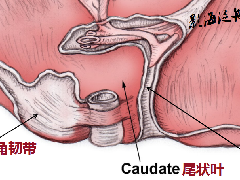

CT:(1)肠壁增厚,增厚的肠壁黏膜面多明显凹凸不平。(2)腔内肿块影,偏心性,呈分叶状或不规则形,与正常肠壁分界清楚,肿块表面可见小溃疡,呈火山口样。(3)肠腔狭窄,且为非对称性。(4)增强扫描可见较明显异常强化。(5)浆膜及临近器官受侵表现。